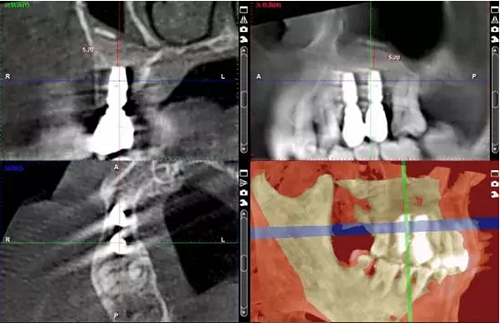

術后當天 術后7個月

術后8個月 術后10個月

術后13個月

術后14個月